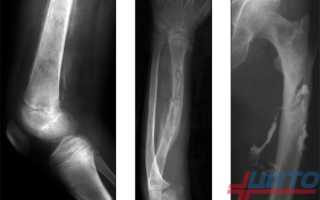

Остеомиелит у новорожденных